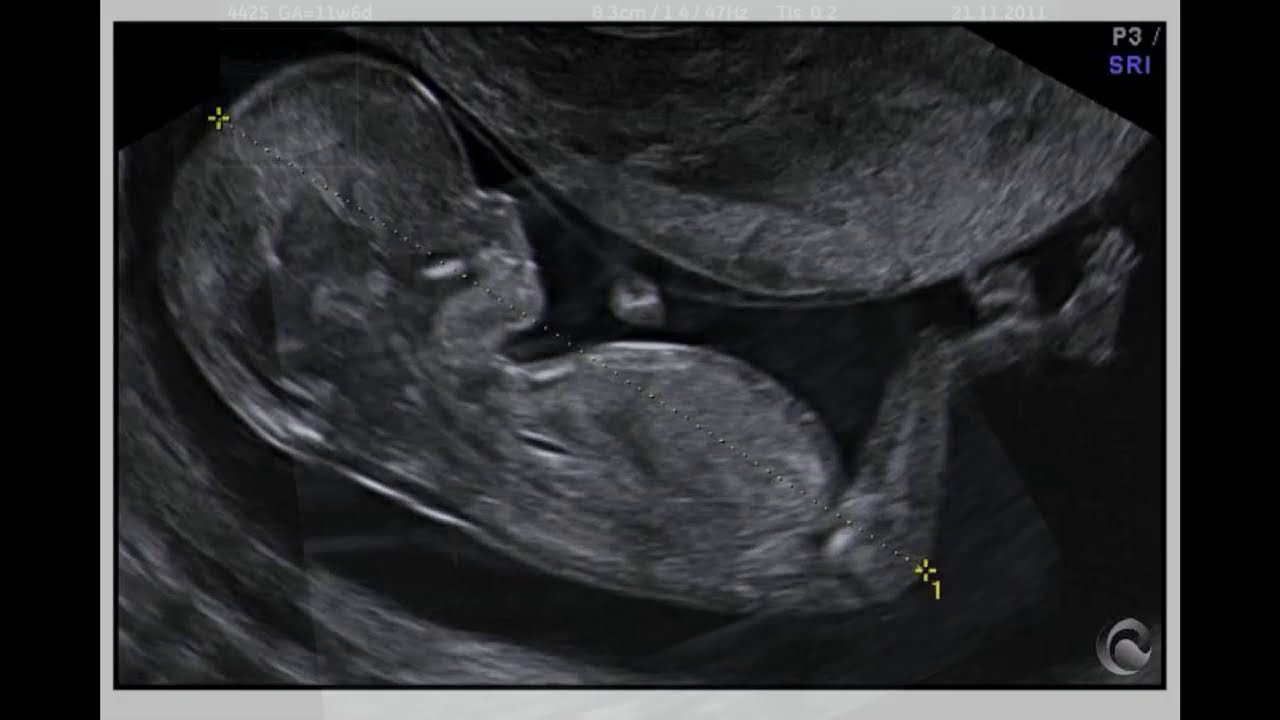

¿Qué es la TRANSLUCENCIA NUCAL?

En este tutorial te platico la historia del surgimiento de la translucencia nucal como un marcador de aneuploidias y te enseño cuales son las especificaciones para medirla de forma correcta.